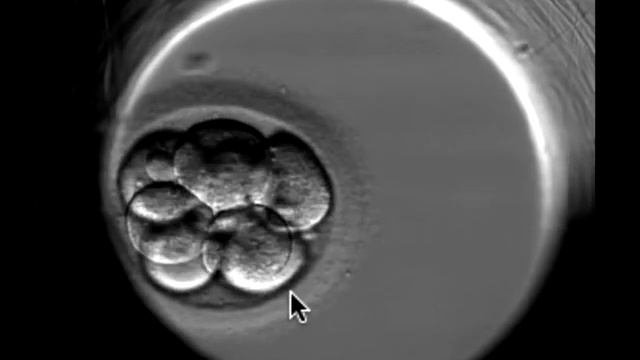

Сегодня я вам хочу рассказать об этом видео, на котором эмбрион развивается в течение 5 дней. На видео вы видите яйцеклетку. Это видео снято через ембри...